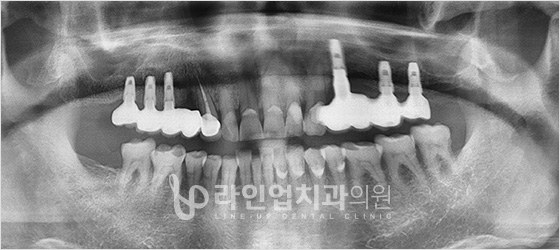

Имплант хийлгэхийн өмнө ба дараах зураг

Before

After

Дээд арааны имплант